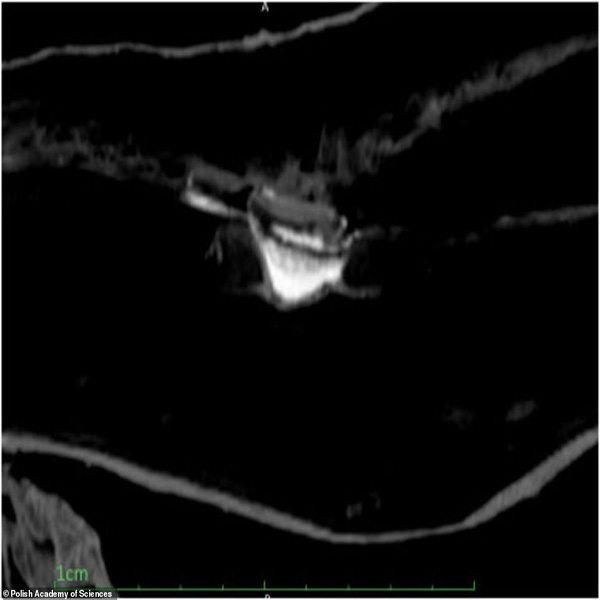

این تیم با استفاده از ترکیبی از سی تی اسکن و اشعه ایکس ، بقایای جنین حدود 26 تا 30 هفتگی را در داخل بدن این زن مومیایی کشف کرد و به این ترتیب نخستین مومیایی باردار جهان شناسایی شد.